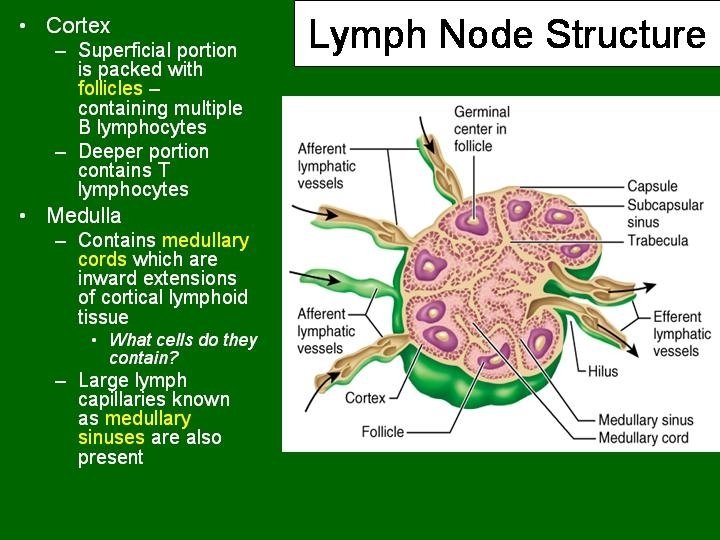

Lymph Node • • • Capsulated Afferent lymphatics “subcapsular sinus” Hilum – blood vessels, efferent lymphatic Cortex and medulla Cortex – Lymphatic nodules, germinal centres – “Paracortex” T-dependent zone • Medulla – Medullary cords and sinusoids M C

LYMPH NODES These are the smallest but most numerous encapsulated lymphoid organs. Scattered in groups along lymphatic vessels , they act as in-line filters of the lymph, removing antigens and cellular debris and adding Igs. Lymph nodes are bean-shaped structures with convex and concave surfaces. The parenchyma consists of a peripheral cortex, adjacent to the convex surface, and a central medulla lying near the depression (hilum) in the concave surface. The connective tissue capsule gives off trabeculae that penetrate between the cortical nodules and subdivide the cortex. Cortex. The cortex is dark-staining owing to the presence of tightly packed lymphocytes. These are suspended in a reticular connective tissue network and arranged as a layer of typical secondary lymphoid nodules (containing primarily B lymphocytes) with germinal centers. The cortex also contains reticular cells, antigen-presenting follicular dendritic cells, macrophages, a few plasma cells, and some helper T cells.

Medulla. Lighter staining than the cortex, the medulla is composed of cords of lymphoid tissue (medullary cords) separated by medullary sinuses. The lymphocytes are mainly small, less numerous than in the cortex. The cords are also rich in reticular cells and fibers and contain many plasma cells that have migrated from the cortex. Paracortical zone. This is the T-dependent region, lying between the cortical lymphoid nodules and the medulla. It contains mainly T lymphocytes suspended in a reticular connective tissue. B lymphocytes, plasma cells, macrophages, and antigen-presenting interdigitating dendritic cells may also be present. Lymphatic vessels. Sinuses (subcapsular, peritrabecular, medullary). Functions: 1. Filtration of lymph 2. Lymphocyte production (lymphopoiesis). 3. Immunoglobulin production.